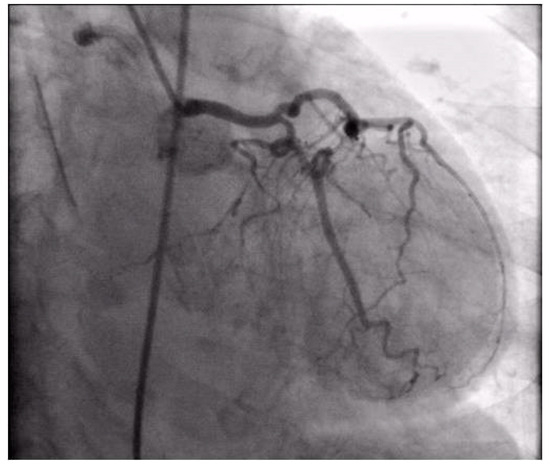

Coronary angiography was performed, showing the left coronary artery (LCA) was without significant lesions (Figure 6). On the right coronary artery (RCA), a subocclusive lesion was registered in the distal segment (Figure 7). Initially, it was thought to be a spasm, but the lesion persisted even after administering nitroglycerin intracoronary. Therefore, a primary percutaneous coronary intervention (pPCI) was performed with the implantation of a drug-eluting stent 16 × 25 mm (Boston Scientific, Marlborough, MA, USA) in the RCA, achieving the optimal result of the intervention (Figure 8).

Figure 6.

Coronary angiography registered left coronary artery without significant stenosis.

Figure 7.

Coronary angiography registered a subocclusive lesion in the distal segment of the right coronary artery.

Figure 8.

Percutaneous coronary intervention was performed, and a drug-eluting stent was implanted in the RCA, with the optimal result.